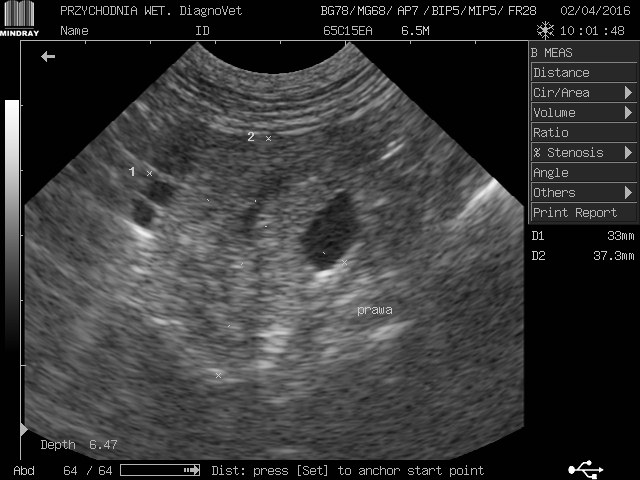

gracja1 Posted August 24, 2017 Posted August 24, 2017 Witam moja ukochana psinka gracja z wyników usg jest w bardzo kiepskim stanie nerki a praktycznie ich brak kwalifikują ja tylko do eutanazji jeżdżę od weta do weta i wszędzie żadnej pomocy.Gracja to piesek mieszany średniej wielkości trafiła do nas w ubiegłym roku ma zaledwie 2 lata.O chorych nerkach dowiedzieliśmy sie tydzień po przyjeździe jak do nas trafiła od początku objawy były ciągłe pragnienie wody i częstomocz decyzja tylko jedna jedziemy do weterynarza tam stwierdzono ze to zwykłe przeziębienie minęło parę dni brak poprawy u pieska powrót do weterynarza.Kazano zrobić badanie krwi moczu i wyszło kreatynina i mocznik podwyższony skierowano mnie na badanie usg tam potwierdziło chore nerki liczne cysty wokół diagnoza eutanazja natychmiastowa.Nie poddałam się minął rok z gracja od tamtej pory jest zemną bawi się biega kocha mnie nad życie lecz od paru dni dziwnie zaczęła się zachowywać jest osowiała mało zjada pije wodę wzięłam ja do weterynarza po diagnozie weterynarze są w szoku ze moja gracja żyję a na wieść o tym we dwoje zaczęli usg i to co zobaczyli to praktycznie brak nerek jedynie cysty do tej pory niewiadomo co tak naprawdę trzyma psa przy życiu i dziwią się ze on chodzi i biega w takim stanie a ja słyszę tylko w kółko pies do usypania zero szans zero leków absolutnie żadnej inicjatywy ze strony lekarza czy to normalnie dlatego jestem tutaj i opisuje swoja sytuacje a gracja leży przy mnie i nikt niepotrafi pomóc.Przesyłam skan usg krótko po przyjeździe gracji do mnie i pierwsze usg proszę o jakieś wskazówki do kogo jechać z kim porozmawiać bo siedzę i tony łez wylewam.Wyniki krwi z dnia 22.08.2017 Kreatynina 8.70mg/dl ,mocznik 300mg/dl 1 Quote